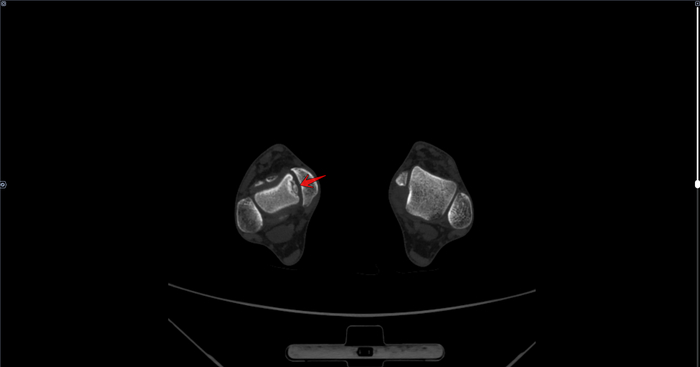

В анамнезе у призывника диагноз- дисплазия тазобедренных суставов, перенесенное оперативное лечение по поводу дисплазии в детстве. По данным рентгенографии костей таза: ШДУ справа 143 град, слева 143 град, сужение суставной щели справа до 3 мм, слева до 3.1 мм, остеофиты по верхне-наружным краям суставных щелей, шейка правой бедренной кости укорочена ,перекос таза вправо. Двусторонние участки разряжения костной ткани в межвертельной области(более выраженно справа)-как следствие перенесенных оперативных вмешательств. Заключение: Coxa valga bilateralis как следствие дисплазии тазобедренных суставов. Вторичный двусторонний коксартроз 1ст.